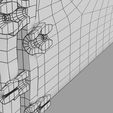

神经肌肉接头示意图